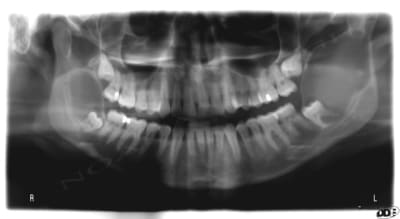

Pano demandé

Ensuite scan

j'ai le scan mais pas ici la corticale linguale est reduite à sa plus simple expression et le kyste remonte sur le trajet du nerf et s'etend aussi en vestibulaire

tu es sur que la 37 n'est pas en cause?

le problème c'est que je n'ai pas revu la patiente pendant 4 ans et que je ne sais pas l'etiologie exacte

je "subis" mon premier problème de dent de sagesse, si j'avais eu à traiter lors du 2° pano ça ne me faisait pas de soucis, mais là!